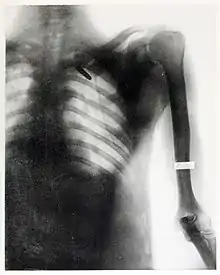

In December 1898, she began to provide services as a radiographer to the United States Army, who had been sending wounded soldiers from the Spanish-American War's Pacific theater back to the United States through San Francisco.[14]

On August 20, 1899, she took one of her most famous radiographs, an image showing a Mauser 7 mm bullet lodged in the brain of John Gretzer Jr., in the region of the left occipital lobe.[12][15] Private Gretzer, of the 1st Nebraska Volunteers, wounded at Mariboa, Philippines on 27 March 1899 during the Spanish–American War. The private later returned to duty as a mail clerk.[16] Accounts of the case were reported in the 1902 edition of The International Text-Book of Surgery and in newspapers.[17] Another case of a bullet lodged in a soldier's skull, X-rayed by Fleischman was also reported in newspapers in 1899.[18]

She received praise for her work during the Spanish-American War from the Surgeon General of the Army George Miller Sternberg.[19] Several of her radiographs were also used by William C. Borden to illustrate his book on the medical use of X-rays in the Spanish-American War.[15]